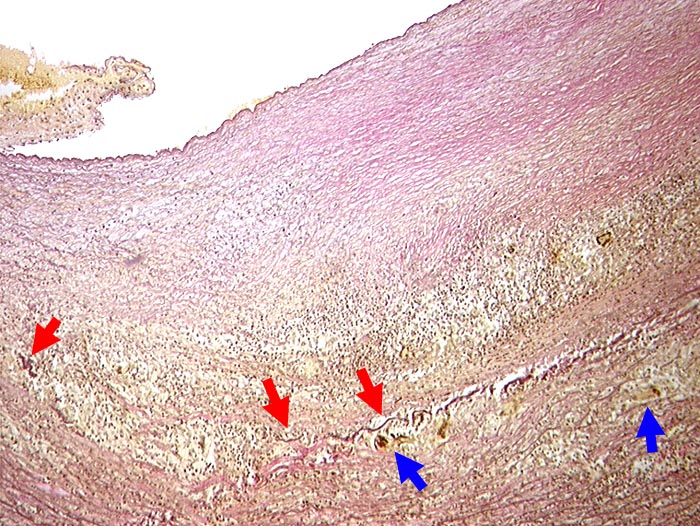

Riesenzellarteriitis der Arteria carotis interna

Dichtes lymphohistiozytäres Entzündungsinfiltrat in Media und Adventitia. ► Riesenzellen phagozytieren die bereits fragmentierte ► Lamina elastica externa.

Primäre Vaskulitis mit Befall grosser Gefässe, bevorzugt extrakranielle Äste der Arteria carotis. Temporalarterie häufig betroffen.